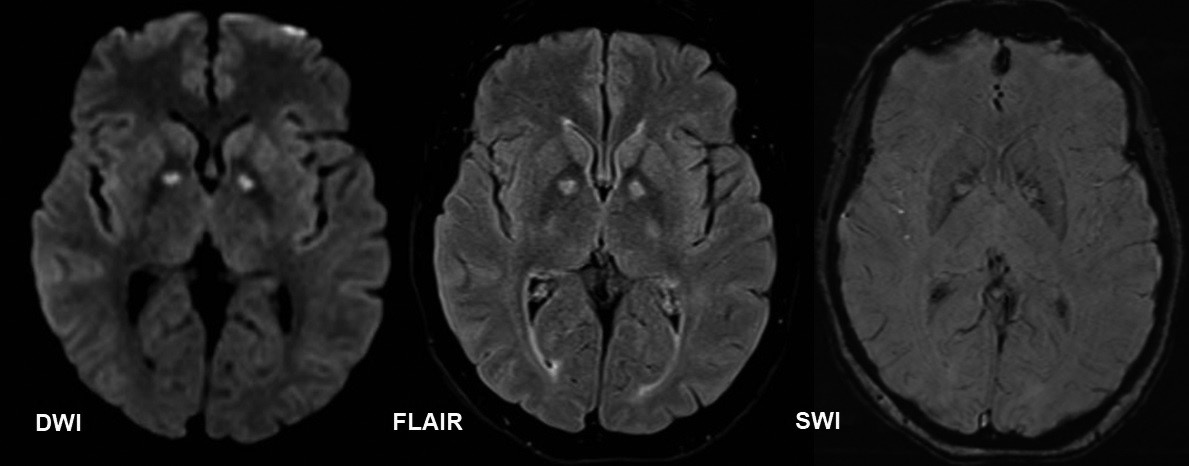

Los estudios de extensión no dan evidencia de alteración metabólica ni de infección intercurrente, una tomografía computarizada (TC) cerebral sin contraste no demuestra alteraciones (figura 1). Se realiza un video electroencefalograma de tres horas que demuestra trazado compatible con encefalopatía leve, sin evidencia de actividad irritativa focal. Se decide profundizar con una resonancia magnética cerebral en búsqueda de otros diferenciales; dicho estudio que se realiza 72 horas posteriores a la tomografía inicial, evidencia lesión isquémica subaguda bilateral en los globos pálidos (figura 2). En los días siguientes la paciente presenta empeoramiento de los síntomas ansiosos y afectivos, manifestando marcada inquietud motora e incapacidad para permanecer quieta, sugestivo de un cuadro de acatisia, el cual se modula con aumento de la dosis de antipsicótico y suspensión del antidepresivo. Progresivamente hay control de los síntomas, mejoría del afecto, regulación del ciclo sueño-vigila, sin presentar nuevas alteraciones de la sensopercepción ni ideas delirantes. Además, y llamativamente, el dolor crónico y la necesidad de consumo de opioides remiten completamente, permitiendo rápidamente el desmonte de la metadona, previamente iniciada para el manejo del TUS. Luego de aproximadamente tres semanas de tratamiento intrahospitalario, la paciente es dada de alta para continuar seguimiento por psiquiatría y toxicología de forma ambulatoria.

Como dato de especial relevancia en este reporte dada la lesión cerebral evidenciada, se ha descrito que entre el 5 a 10% de los usuarios de heroína pueden presentan lesiones isquémicas en el globo pálido (8,9). Inclusive, en estudios por autopsias, se ha reportado que hasta el 10% de los pacientes que sufren de adicción a opioides presentan lesiones de tipo hipóxico isquémicas bilaterales en los globos pálidos (10). Considerando la baja sensibilidad de la tomografía simple para identificar lesiones isquémicas cerebrales (11), las imágenes obtenidas mediante resonancia magnética cerebral son fundamentales para llegar a un diagnóstico en estos casos.